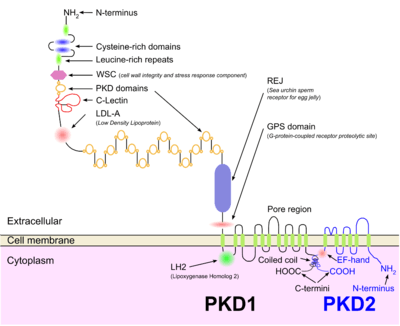

There are three genetic mutations in the PKD-1, PKD-2, and PKD3 gene with similar phenotypical presentations. Gene PKD1 is located on chromosome 16 and codes for a protein involved in regulation of cell cycle and intracellular calcium transport in epithelial cells, and is responsible for 85% of the cases of ADPKD. A group of voltage-linked calcium channels are coded for by PKD2 on chromosome 4. PKD3 recently appeared in research papers as a postulated third gene.[3][9] Fewer than 10% of cases of ADPKD appear in non-ADPKD families. Cyst formation begins in utero from any point along the nephron, although fewer than 5% of nephrons are thought to be involved. As the cysts accumulate fluid, they enlarge, separate entirely from the nephron, compress the neighboring kidney parenchyma, and progressively compromise kidney function.[8]

Some indications are that both autosomal and recessive polycystic kidney disease cyst formation is tied to cilia-mediated signaling that is irregular. Further, the polycystin-1 and polycystin-2 proteins appear to be involved in both autosomal and recessive polycystic kidney disease due to defects in both proteins.[11] Both proteins have communication with calcium channel proteins this causes reduction in resting (intracellular) calcium and endoplasmic reticulum storage of calcium.[12] The disease is characterized by a ‘second hit’ phenomenon, in which a mutated dominant allele is inherited from a parent, with cyst formation occurring only after the normal, wild-type gene sustains a second genetic ‘hit’, resulting in renal tubular cyst formation and disease progression.[13] Specifically, PKD is thought to result from defects in the primary cilium, an immotile, hair-like cellular organelle present on the surface of most cells in the body, anchored in the cell body by the basal body.[13] In the kidney, primary cilia have been found to be present on most cells of the nephron, projecting from the apical surface of the renal epithelium into the tubule lumen. In response to fluid flow over the renal epithelium, the primary cilium is bent, resulting in a flow-induced increase in intracellular calcium.While it is not known how defects in the primary cilium lead to cyst development, it is thought to possibly be related to disruption of one of the many signaling pathways regulated by the primary cilium, including intracellular calcium, Hedgehog, Wnt/β-catenin, cyclic adenosine monophosphate (cAMP), or planar cell polarity (PCP).function of the primary cilium is impaired, resulting in disruption of a number of intracellular signaling cascades that produce dedifferentiation of cystic epithelium, increased cell division, increased apoptosis, and loss of resorptive capacity.[8][13]